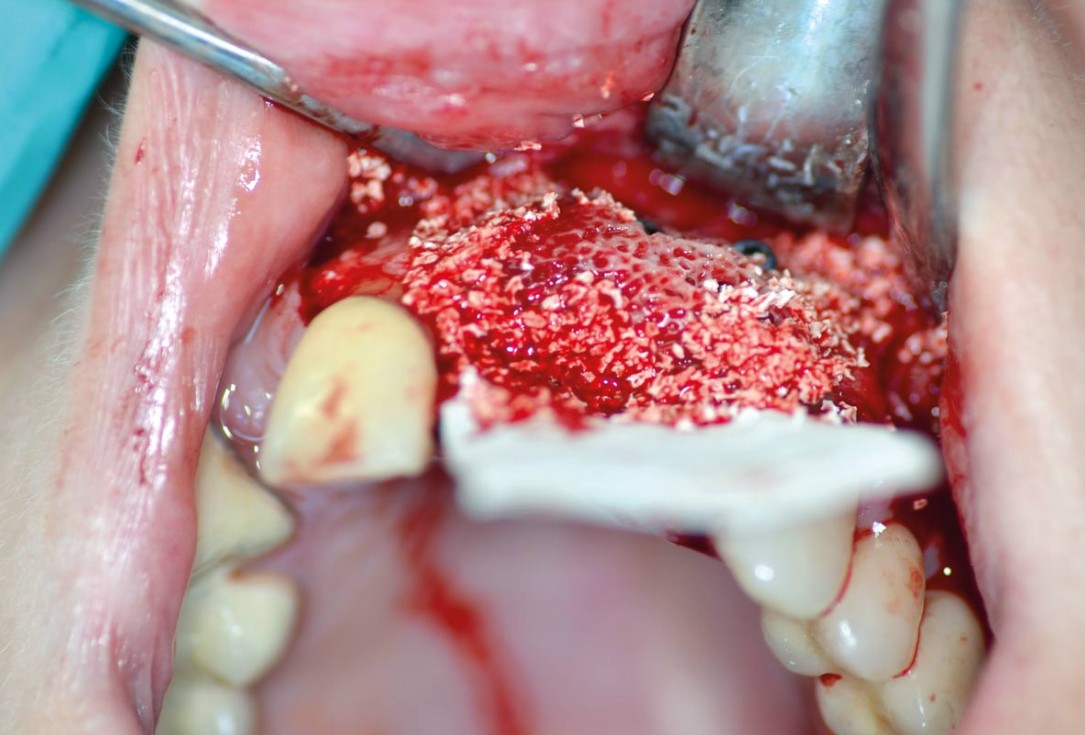

Regeneration of a 9 mm vertical bone defect with cerabone®, autologous bone and S-PRF –  Dr. A. Eslava